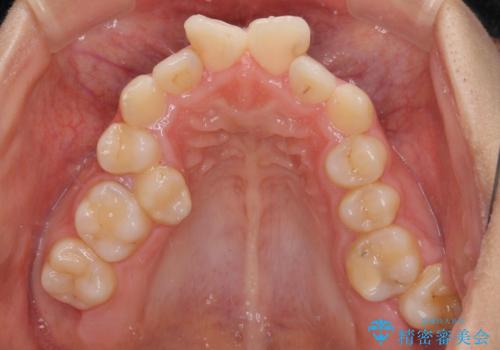

上顎は歯列不正が強く、右側臼歯部の咬み合わせは歯1本分ずれている状態でした。

補助装置を用いて奥歯の咬み合わせを改善しながら歯列を後方に移動させ、上下左右第一小臼歯を4本抜歯することで八重歯や口元の突出感を改善することとしました。